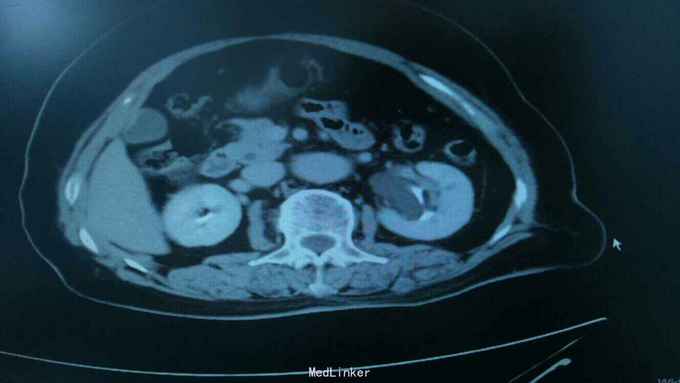

68岁,女性。 主诉:左侧腰痛1年,加重1个月。 病史:1年前无明显诱因出现左侧腰痛,无恶心呕吐,无肉眼血尿。1个月前加重,于外院查泌尿系彩超显示:左肾积液,输尿管显示不清。

查体:腹软,无压痛,左肾区叩击痛(+-),右侧肾区叩击痛(-)。

诊断:双肾盂旁囊肿 治疗:因患者肾盂未明显受压,疼痛症状不明显,等待观察,暂未予处理。

双侧同时出现的病例并不多见,临床只能通过泌尿系统CTU或增强CT加以鉴别,彩超无法区分肾盂积水及盂旁囊肿。